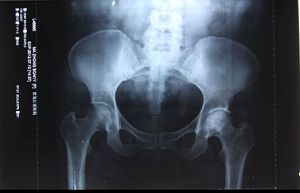

我清晰的记得,一九九九年二月六日最后那次确诊,当时我的好姐妹七姐把我背到哈尔滨北方股骨头坏死研究所二楼,我就在地上爬着走。在医生办公室,身子趴在地板上,头吃力的仰望着沉默不语的大夫。他对这次诊断没细说,怕我上火,实际上当时确诊为双侧股骨头坏死二期。怀着一线希望,我怯生生的问着:“大夫,我什么时候再来拍下一回片子啊?”医生木然的说:“八个月以后吧!”

二零零零年三月,我到哈尔滨北方股骨头坏死研究所,我要取回我的病历和当时拍的CT片。我见到了曾给我看过病的研究所所长,见我走進来他们很震惊:你不是那个双侧股骨头坏死二期,在地上爬的那个患者吗?我说是啊。他惊讶的说:“你能走了?”我说:“你看我这不是走着来的吗”!张医生说:你走一个我看看?他忘了我是走着進去的。我就在屋里再给他走,我说我在家啥都能干了,我盖房子,打工什么都能干。他问我我就乐,他说搞的什么名堂快说说。张医生马上查找我的病历,一看只拿了一副药,就说:“你这绝不是用药的结果,快说说你是怎么好的?”

张医生商量着我再拍一个片子,看看我的腿到底啥样了,我说我好了还花那个闲钱?医生说不要钱。

我说那我也不拍,好象我炼法轮功还不信任这个功法似的。屋里的几个病人听说我是背着来的,现在好了,都想看看我这股骨头恢复得如何。那些人也说:孩子你拍一个我们也看看啥样了。在大家的劝说下我拍了片子。拍完这个片子医生把最初来看病拍的那个片子拿出来对照,发现两个片子一模一样,大夫说你这腿也没好啊?看你这股骨头还跟烂土豆似的。看片子我的股骨头并没有变化,但我人却行动自如了。医生让我走、蹲给他们看,在我身上看不出股骨头坏死患者的任何症状,要不是张医生和片子作证,在场的所有医生和患者怎么会相信呢?我说这法轮功可神奇了,看你信不信,你信就有人管你。我说那片子有没有股骨头关我啥事呀,我能走我不疼就行呗,那我自己不疼我不知道啊。医生也说:对对,你不疼就行呗,管他片子啥样呢。

一九九九年二月六日我第一次去哈尔滨北方股骨头坏死研究所,也是最后一次在医院检查确诊,见到的就是所长,他是一个很正直很讲医德的医生。二零零零年三月份我去过他们研究所重新拍了一个片子,片子所展现的还是股骨头坏死,但是那次我是一个完全恢复了健康的人去拜访他的,他也奇怪,怎么片子没有变化,人却不一样了。当时在他身边的一位年轻的医生说:这个病例可以记录在我们研究所的历史上了,所长却说:那不行,这个患者的病不是我们治好的,她是炼法轮功好的,和我们的治疗没有一点关系。

那篇文章,黑龙江省公安厅的人也看到了,去研究所调查我的事是否属实,张连喜医生实话实说的讲述了他亲眼见证了大法的神奇。医生把我的病例号(一九九九年三号)和二零零零年三月份拍的片子对比着讲给他们,两次拍片的结果都写着“双侧股骨头坏死”,但是炼法轮功后人是个健康的人了。省公安厅的人在那里也明白了事实真相,这件事就不了了之了。

二零一二年我又一次去了哈尔滨北方股骨头坏死研究所取片,那位所长又给我拍了个片子,结果仍然是股骨头坏死的症状。

2、黑龙江省医院

我修炼后三天就把那么严重的股骨头坏死炼好了,我去了修炼前曾经看过病的省医院拍片,医学影像科的医生张明磊给我拍完片子,那个大夫就在X光检查报告单上确诊的“股骨头坏死”后面打了个问号,在诊断书的下面写着:“观察”两个字。但是他写出病例了,盖的章。他给我做各种检查我都正常,走道,蹲起都行,他很纳闷。我就问他,问号是啥意思?他说:你是股骨头坏死。你这不是好了吗?我说我们家人让我花钱来拍片,就想看看片子怎么样。片子是啥样呢就给写啥样,家人只想要片子。你这问号是啥意思,我到底是不是股骨头坏死?他说:是,是股骨头坏死。但是你哪都不疼,你不都正常了吗?他也不明白是怎么回事。他对我提出的问号很后悔,大夫的名章已经盖上了没有办法再改变了,也只好那样了,他一再说:是股骨头坏死,是股骨头坏死。

二零一二年七月十号在黑龙江省医院检查股骨头坏死的诊断。

二零零五年我在砖厂干活时,偶尔碰到一个当地的医生,他早听说了我的事,但是他没信,非要我拍个片子看看,我去了区医院,拍完片子后那个人问我:你吃啥药好的呀?我告诉他我是炼法轮功炼好的。拍片子的人说:哎呀,你太幸运了(意思是说,你的股骨头这样你还能走路)。等片子拿给大夫看的时候,那大夫看看片子瞅瞅屋里的人问:人呢?我问他:啥人哪?大夫说:病人呢?我说我就是。他以为我没听懂他的话呢,接着还问:我说的是拍片子的人,你听不懂话呀?我问的是拍片子的那个人!我也郑重的告诉他:我就是拍片子的那个人!那大夫很吃惊的问:啊!你是咋好的?我说我是炼法轮功炼好的。

这大夫就紧忙的把我的一堆片子一边往袋子里装,一边说:哎呀妈呀,你快回家炼去吧。我就问那大夫:我在你这花钱拍片子,你得给我看看我这片子啥样啊。大夫说:这片子上是没好,但是你这不是好了吗!你快回家炼去吧。

我把片子拿给那个当地医生看,他一看片子就说:你确实是股骨头坏死,这是真的呀。护士不怎么会看片子,就问那个大夫:这片子咋看能看出是股骨头坏死啊?那个大夫说:你看这侧,比较好的那个地方,这上面有骨纹,你再看这侧是透亮的,没有骨头也就没有骨纹。那大夫在事实面前终于相信了,他说:你这功炼得好,你好好炼吧!

二零零四年左右,我在哈市做家政服务,碰巧这个家庭的主人是哈尔滨医科大学附属医院CT室主任,他叫魏庆堂,是这个医院的权威,退休后返聘回去的。他看到我在他家做的家务很利落就对我说:你的身体挺好。我说我得过双侧股骨头坏死,炼法轮功炼好了。他马上说:那要是炼法轮功能治病还要医院干啥呀?都炼功得了呗,你那是误诊,我根本不相信那些。再说了股骨头坏死是世界上疑难病症之一,没有特效药,根本就不可能好到那种程度,上蹦下跳的跟正常人一样?你那是误诊,根本就不是股骨头坏死啊。

我说我在医大,还有几个地方都看过病。他告诉我:医大门诊的那些人都是我的学生。然后他对我说:星期日下午患者少,你去医院我给你查一下。我和魏医生的儿媳、孙子如约去了医大的CT室,魏医生给我做了三样CT,腰部、腹部、臗部。我原来附件炎、肾炎、妇科病都很重,他说你的腹部没有病;又拍腰,说你没有腰间盘突出,腰也没病;然后又拍臗部,他一下就看到了,他惊讶的说:啊!你确实是股骨头坏死,而且还很严重。股骨头烂的只剩一半了,半个,扣不住了,就是这个轴没了呀。但魏主任说:“你好了,你的骨质密度特大,你的骨质特结实。”

我说:“这股骨头都烂没了,怎么能说好了呢?”魏主任说:“我们的这台CT机一千多万元呢,能把骨头切片到130个横断面看骨质的内部,你股骨头的密度特别大。所以我说你好了。”他又说:“现在你的片子上股骨头的这个样子,应该是根本就无法抬腿的。”我当时就把腿给他抬的高高的,我问他:你说咋抬吧?他说:这也太神奇了。

魏主任惊讶的无话可说,最后喃喃自语:“我从来没反对过法轮功,我从来没反对过法轮功。任何一个功法对祛病健身都有好处,都有好处。”但是魏主任很纳闷片子上一面是股骨头坏死的状态,一面是骨质的密度特大。